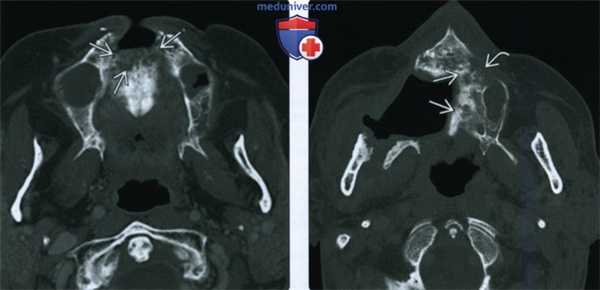

(Слева) При аксиальной КТ в коаном окне у пациента, получавшего лучевую терапию по поводу ПКР носовой перегородки, определяются литические изменения в передних отделах верхней челюсти, визуализируется фрагмент разрушенной кости.

(Справа) При аксиальной КТ в костном окне у другого пациента определяются изменения, обусловленные резекционным вмешательством на небе справа, видны также очаги литического и склеротического характера в верхней челюсти слева, которая также была подвергнута облучению. Верхняя челюсть относительно устойчива к лучевому воздействию и мало подвержена ОРН. Лучевые признаки ОРН верхней челюсти идентичны таковым для нижней челюсти, других костей лицевого скелета и основания черепа.

(Слева) При аксиальной КТ в костном окне у пациента, получавшего лучевую терапию по поводу плоскоклеточного рака носовой перегородки, визуализируется очаг литического характера в передних отделах верхней челюсти, представляющий собой треугольный участок деструкции костной ткани.

(Справа) При аксиальной КТ в костном окне у другого пациента определяются признаки выполненной резекции неба справа, а также изменения смешанного (склеротического и литического) характера в верхней челюсти слева, которая подвергалась облучению. Верхняя челюсть является относительно устойчивой к ионизирующему излучению, в ней редко возникает остеорадионекроз. Лучевые признаки идентичны таковым при поражении других костей лицевого скелета и основания черепа.